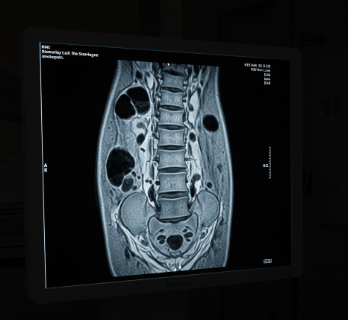

📸 Step 2: 영상 검사

X-ray 촬영: 척추 뼈의 전반적인 상태 확인

MRI 검사: 신경과 연부조직까지 정밀 진단 (가장 정확)

CT 촬영: 뼈의 구조를 3D로 확인

💡 진단 기준

척추관 직경이 **12mm 이하**면 협착증으로 진단

신경근 압박 정도와 증상의 연관성 확인

다른 질환(디스크, 혈관 질환)과의 감별 진단